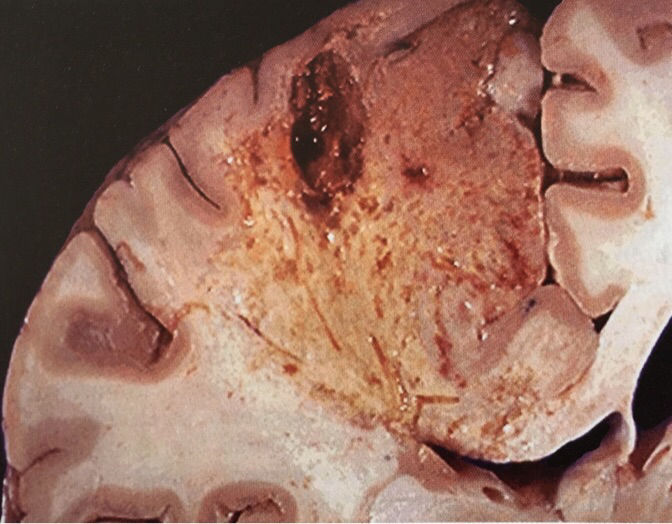

Necrose caracterizada por digestão de células mortas, resultando na transformação do tecido em uma massa viscosa líquida. Ocorre em infecções bacterianas e em hipóxias do SNC. Necrose liquefativa

Descreva Necrose liquefativa. Infarto no cérebro.